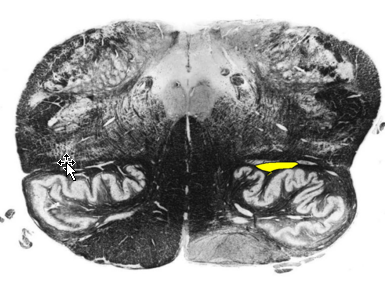

Describe the Pyramidal (Motor) Decussation

Location

Fiber Destiy

Somatotopy of Decussation

Location:

ventral surface of the medulla; disruption of the anterior median fissure

Fibers Destiny Here:

80-90 percent of corticospinal tract fibers decussates (L CST)

8% descend ipsilaterally → anterior funiculus → decussate segmentally (Anterior CST)

2% descend ipsilaterally to contribute to the lateral corticospinal tract (tract of Barnes)

Somatotopy of Decussation:

Upper Extremity fibers: Rostrally

Lower Extremity fibers: Caudally

THUS: iscrete lesions in the pyramidal decussation may produce different and somewhat unusual patterns of weakness.